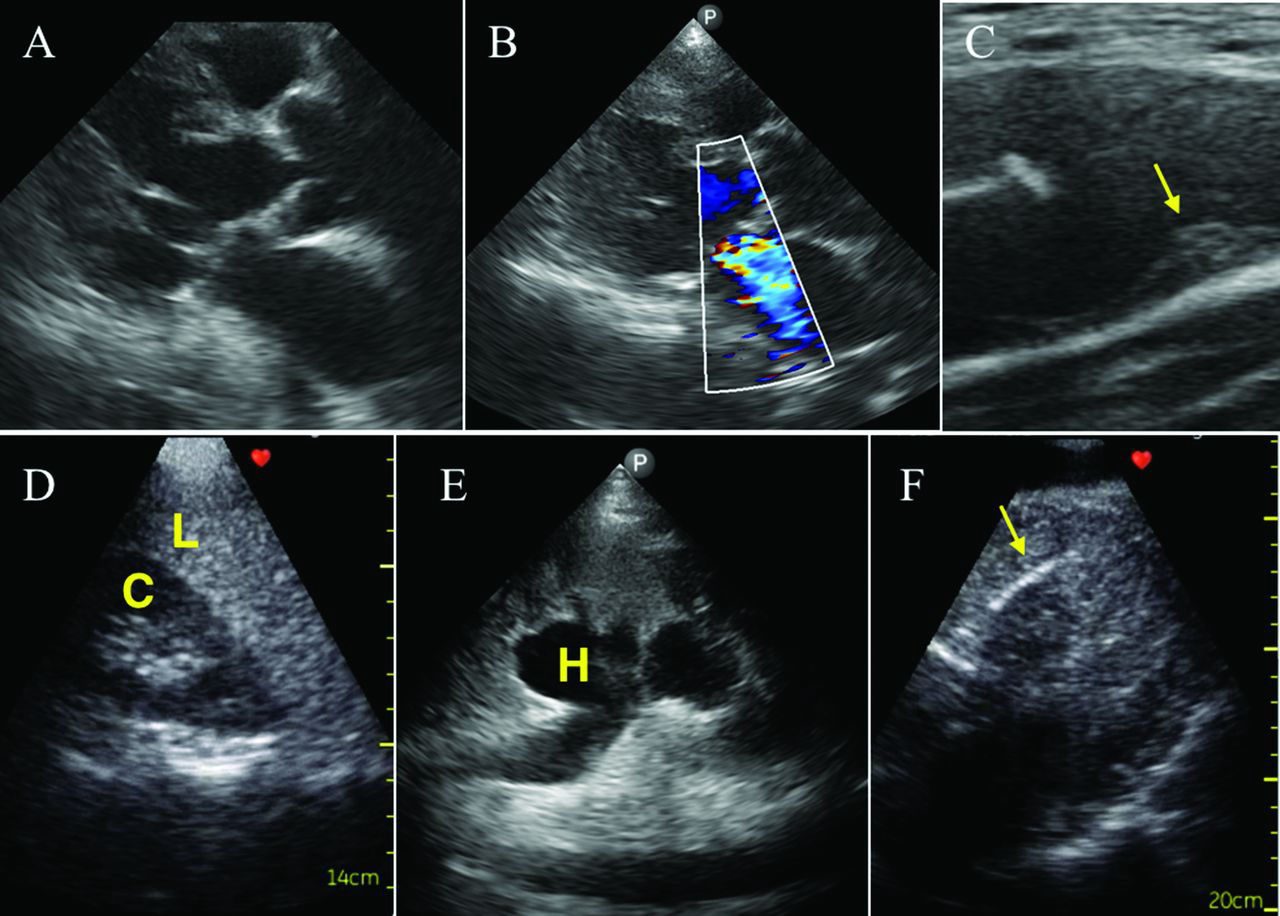

- APLICACIÓN: es complementario al examen físico a modo de identificar la presencia o ausencia de una alteración patológica en el paciente.

- USOS MÚLTIPLES: puede usarse durante la resuscitación (RCP), diagnóstica, para guiar procedimentos y monitoreo del paciente.

- ÁREAS Y PROTOCOLOS- RCP (Rush), pulmonar, cardiaco, vasos sanguíneos, abdominal, emergencias, trombosis venosa, tejidos blandos y tiroides.